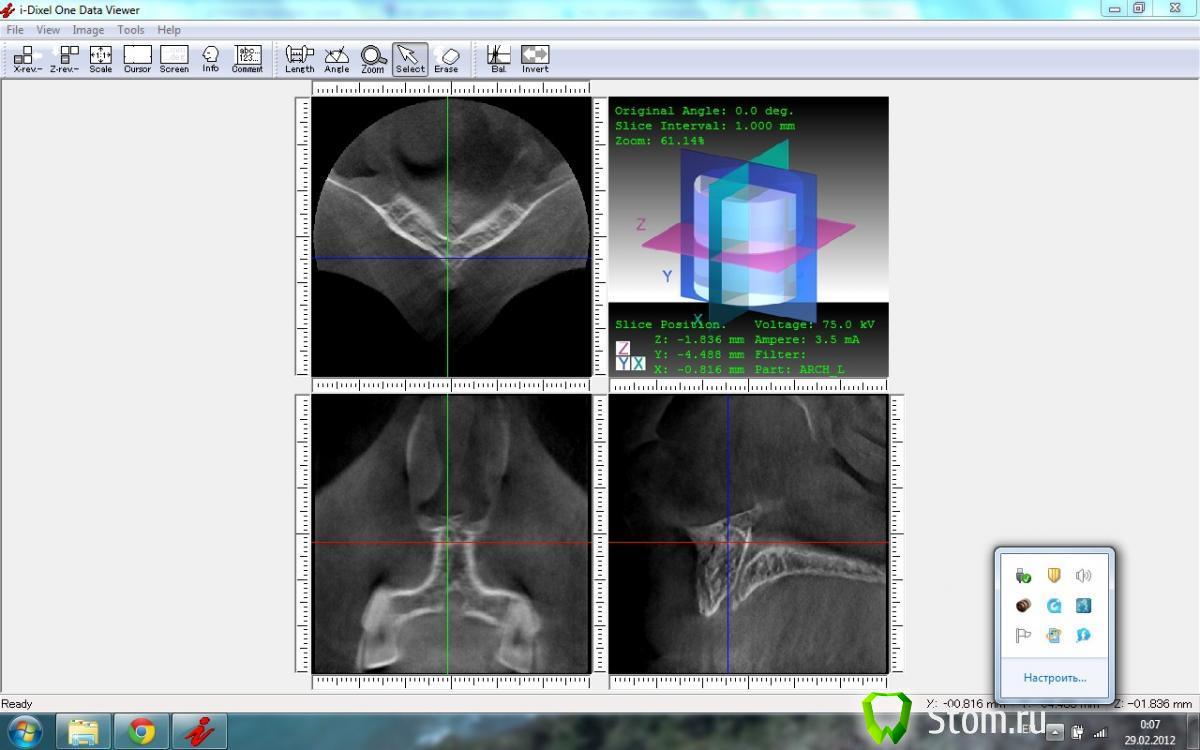

Jedi Опубликовано 28 февраля, 2012 Автор Поделиться Опубликовано 28 февраля, 2012 Вот КТ пациента Ссылка на комментарий